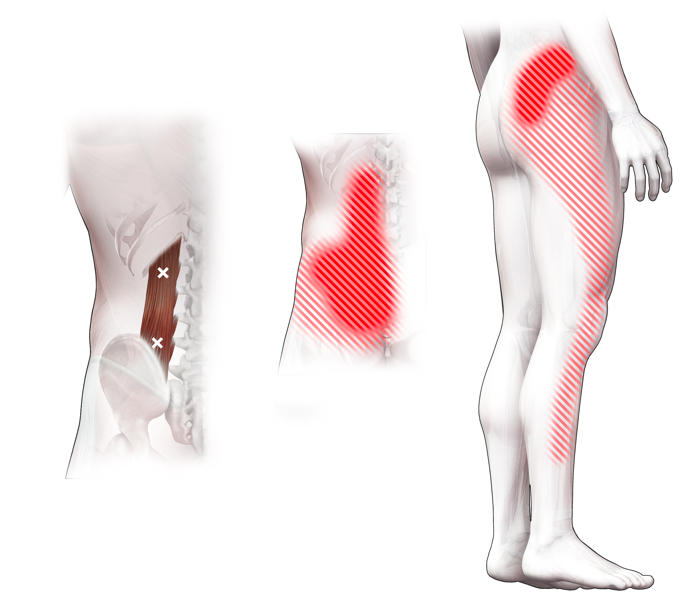

Klachtgebied

Klachten

klachten

Spieren (Nederlands)

Spieren (nederlands)

Spieren (Latijn)

Spieren (latijn)

Trefwoorden

Trefwoorden